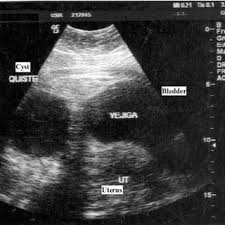

Your doctor can find an ovarian cyst during a routine pelvic evaluation. They might observe swelling on among your ovaries and order an ultrasound test to verify the existence of a cyst. Surgery for a worsening medical condition or to check for cancer. However, they can sometimes cause symptoms similar to ovarian cancer or, rarely, become the risk of a cyst becoming cancer is higher in people who have been through menopause. Ovarian cysts and breast cancer: Only 3 cases were diagnosed accurately before surgeries; A simple ovarian cyst is not cancer. Ovarian cysts are either benign or malignant. Current research suggests this cancer begins in the fallopian tubes and moves to the ovaries, the twin organs that produce a woman's eggs and the main source of the female hormones estrogen and progesterone. Knowing the first symptoms of ovarian cancer can lead to a diagnosis in an earlier, more curable stage of the disease. There are more actual cases of olive leaf. A cyst on your ovary can be found during a pelvic exam. Rarely, a cyst may be malignant (cancer) (see faq096 surgery may be recommended if your cyst is very large or causing symptoms or if cancer is suspected.

What Does Ovarian Cancer Look Like / What are the Signs & Symptoms? - National Ovarian Cancer ... - Wednesday 25 february is ovarian cancer awareness day. . Most ovarian cysts go away with time. This type of cancer can occur in women who still have their ovaries, but it is of more concern for women who have had their ovaries removed to. What does ovarian cancer look like on an ultrasound? Like ovarian cancer, ppc tends to spread along the surfaces of the pelvis and abdomen, so it is often difficult to tell exactly where the cancer first started. I'm sharing my story in the hope of raising awareness about this devastating disease, and to help raise funds for important australian medical research currently being. Department of health and human services national institutes of it is the most common type of ovarian cancer. What does ovarian cancer look like on an ultrasound? Ovarian cancer is highly curable if it's diagnosed and treated early, but the symptom...